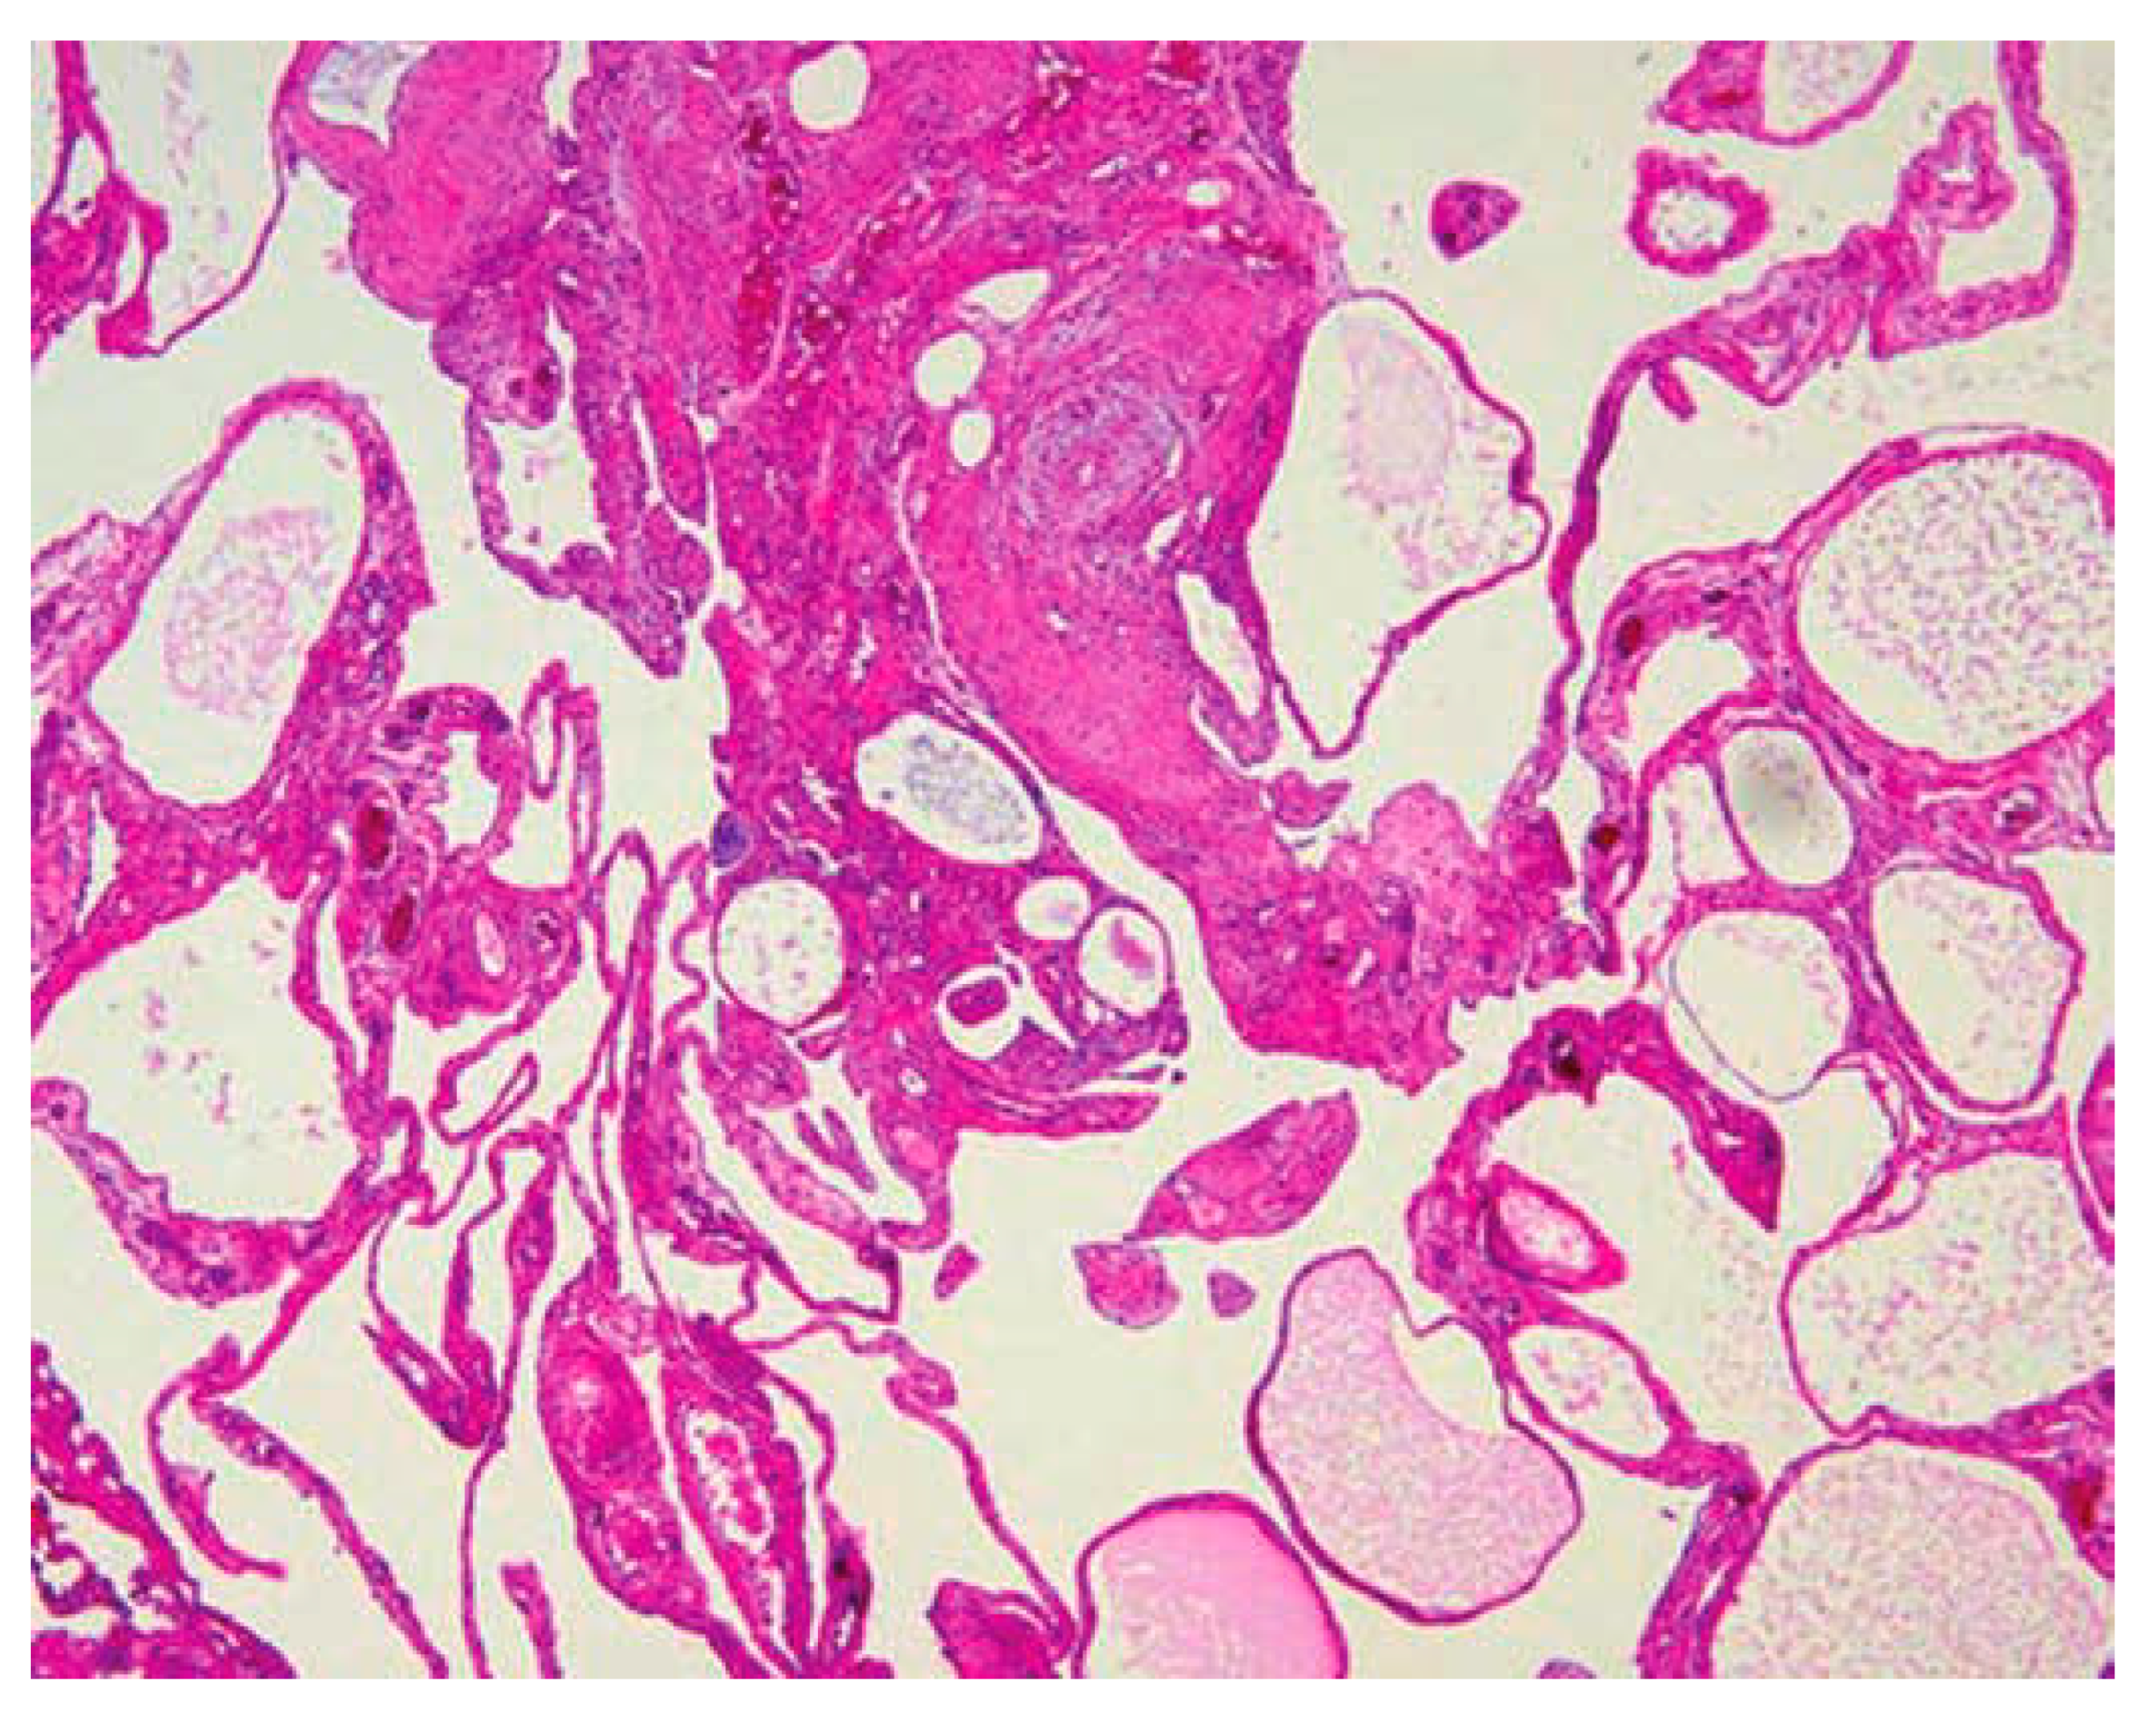

Histopathology

The specimen submitted for histopathological examination yielded crucial insights into the nature of the observed abnormalities. Upon careful analysis, the examination revealed the presence of neoplastic acini and micropapillae within the serosa and muscularis propria. This indicates a significant involvement of these tissues by abnormal cellular growth, suggesting a complex pathology within the affected area.

Furthermore, the examination identified lymph vascular invasion, indicating the infiltration of neoplastic cells into the lymphatic and vascular systems. This observation underscores the aggressive nature of the pathological process, with potential implications for disease progression and spread to other regions of the body.

Upon closer inspection of sections obtained from a specific nodule, additional noteworthy findings emerged. A cyst was identified, its lining composed of neoplastic cells organized into micropapillae. This distinctive architectural pattern within the cyst suggests a characteristic manifestation of the underlying pathology. Moreover, the presence of necrosis in the center of the cyst adds another layer of complexity, indicating areas of tissue death and potential implications for the overall prognosis.

In light of these comprehensive findings, a conclusive diagnosis of peritoneal mesothelioma was established. This diagnosis encapsulates the nature of the observed abnormalities and provides a critical framework for understanding the disease process. The detailed histopathological examination not only aids in confirming the presence of peritoneal mesothelioma but also provides valuable information for guiding subsequent treatment decisions and prognostic considerations.

Preprints 94567 g006